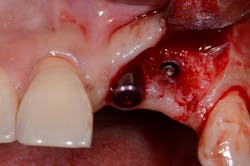

If the occlusal forces delivered to the implant-abutment-crown complex exceed the screw’s clamping ability, this may result in either its loosening (figures 1a and 1b) or, in more severe situations, fracturing of the screw (figures 2a–2c). Clinicians often indite the occlusion as being the primary culprit for the problem; however, in a number of instances, this may not be the case. The cause of screw loosening could also be due to using aftermarket parts, which do not have the precise fit of those made by the manufacturer of the implant.7